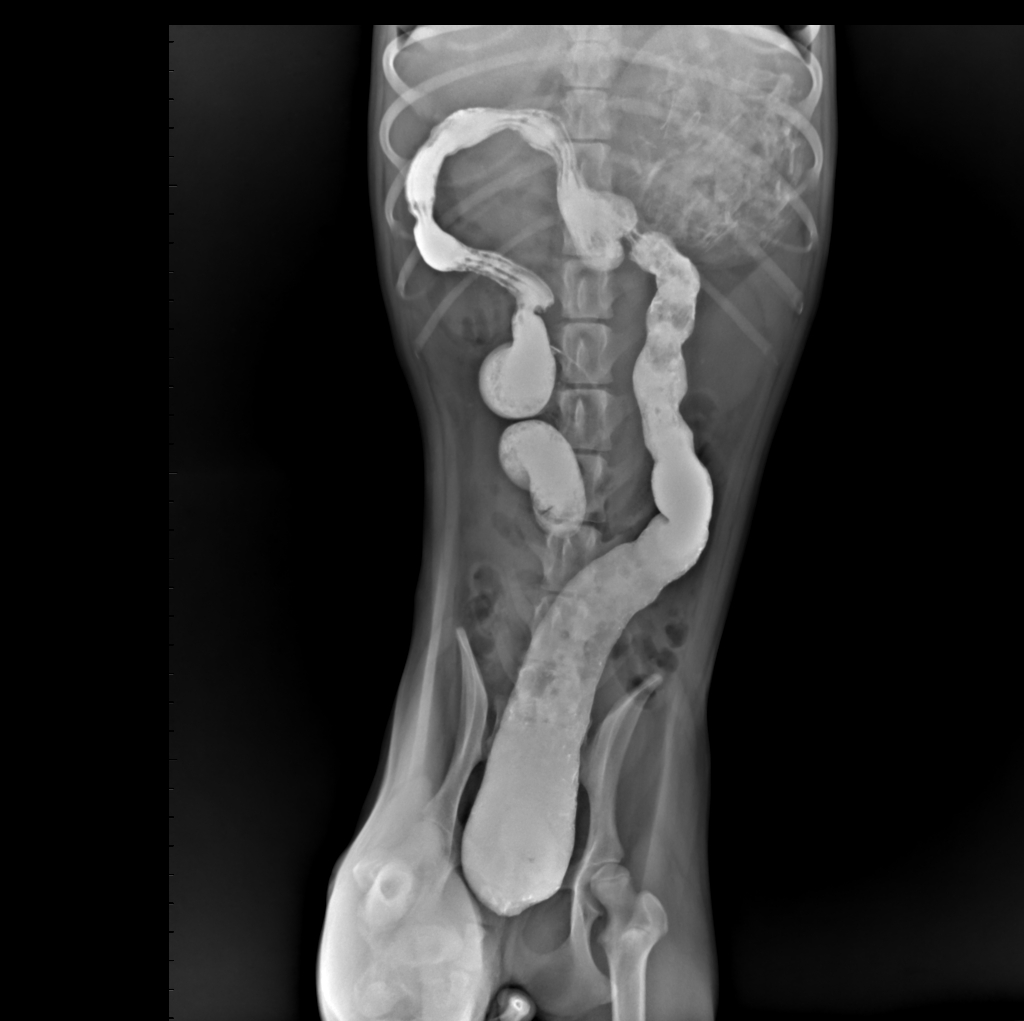

结肠灌肠造影正位片